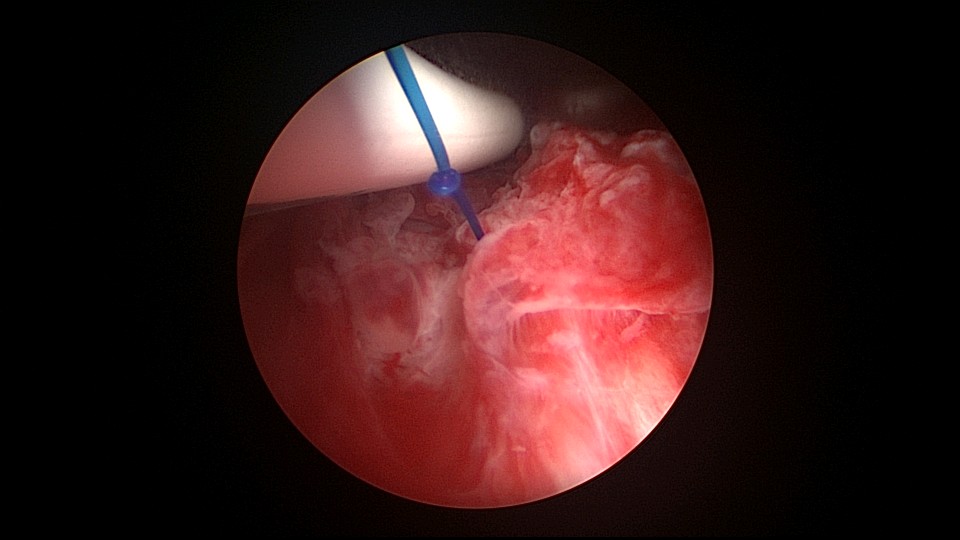

患者42,G3P1,顺产1次。子宫腺肌症伴腺肌瘤,逐渐加重的痛经,2024年11月起皮下注射亮丙瑞林3个周期,出现潮热出汗症状。2025年4月,要求放置曼月乐环并固定,子宫后位,宫深9cm,宫腔上段右侧粘连,宫腔下段宽大。4-0不可吸收线将曼月乐缝合固定于宫腔上段后壁,缝线上靠近曼月乐间距1cm左右打3个结,缝合1针,将1个线结拉过缝合处肌层,利用子宫肌层线结卡压固定曼月乐,避免打结推结。术后多次复查B超,曼月乐位置正常,环顶端距宫底1.6cm。